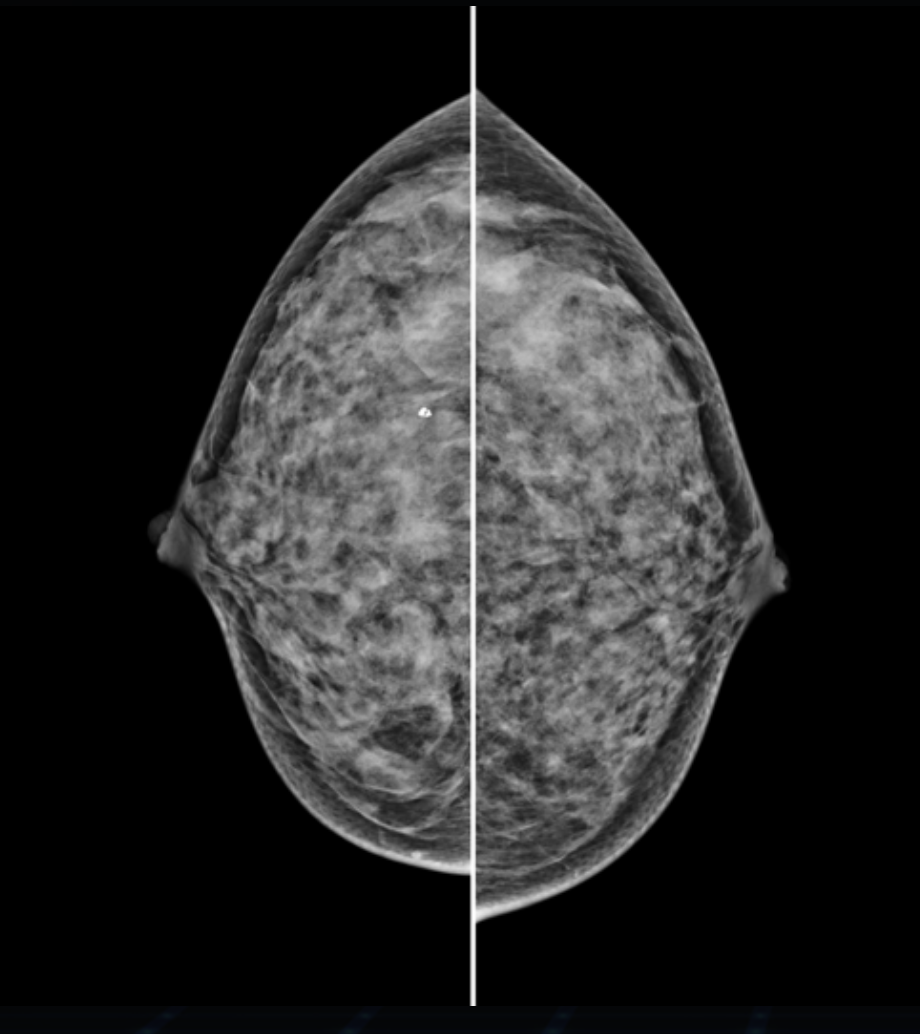

Detektor cyfrowy FFDM

Nowoczesny detektor cyfrowy o wysokiej czułości i rozdzielczości, zapewnia precyzyjne odwzorowanie detali anatomicznych, w tym mikrozwapnień i zmian strukturalnych miąższu.

Tomosynteza 3D

Hestia została zaprojektowana jako system modułowy, który umożliwia rozbudowę o tomosyntezę piersi – warstwowe obrazowanie 3D, zwiększające wykrywalność zmian.